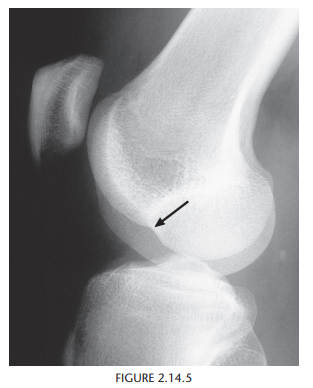

Osteochondritis dissecans (osteochondrosis) of the medial femoral condyle

An osteochondral fracture that was initially caused by shearing, rotatory, or

tangentially aligned impaction forces

semicircular lucency, with an adjacent bony fragment,

on the lateral aspect of the medial femoral condyle

(arrows)

Encircling fluid or focal cystic areas between the medullary canal and the fragment on MRI suggests a potentially loose or unstable fragment.